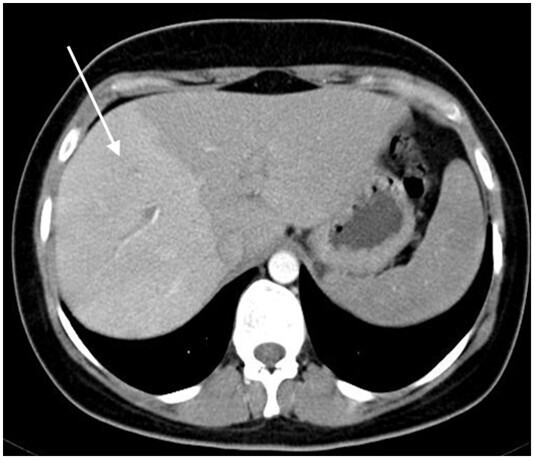

Dysmorphie hépatique

Classiquement, la dysmorphie cirrhotique associe une atrophie du foie droit et du segment IV, une hypertrophie du lobe gauche et du segment I, et des contours bosselés. En cas de maladie vasculaire, la dysmorphie est différente et il est important de comprendre que les zones qui s’atrophient sont celles qui souffrent le plus. Ainsi  :

• en cas de thrombose porte segmentaire ou lobaire, la zone concernée s’atrophie progressivement  ;

• en cas de maladie vasculaire présinusoïdale (par exemple MVPS ou thrombose porte), on observe volontiers une atrophie du foie périphérique, un segment IV de taille normale ou augmentée, des contours lisses du foie (fig. 2)  ;

• en cas de maladie vasculaire post-sinusoïdale (par exemple syndrome de Budd-Chiari), la dysmorphie est plus variable, dépendant des atteintes veineuses. Le segment I est très hypertrophié dans plus de 50  % des cas.